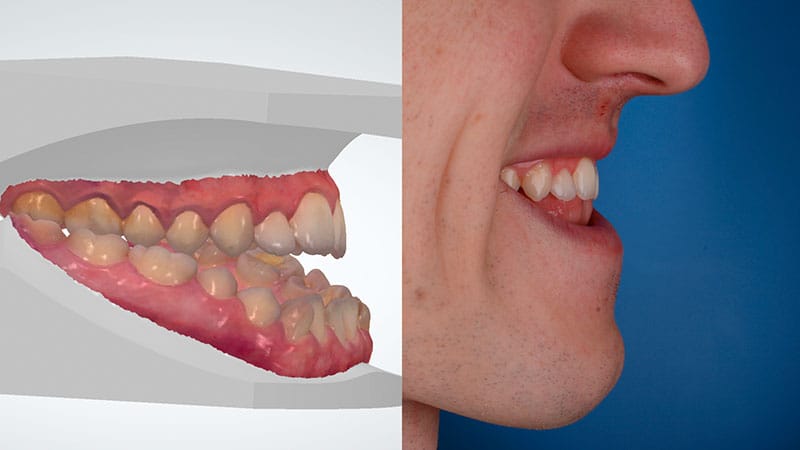

Te ofrecemos dos métodos de Ortodoncia Quirúrgica para corregir problemas severos de maloclusión y estructura facial, con un enfoque personalizado y adaptado a las posibilidades biológicas de cada persona.

Si te preocupa la forma de tu rostro o tienes una discrepancia ósea severa, este tratamiento combina ortodoncia y cirugía maxilofacial para lograr una armonía facial y funcionalidad óptima. En Clínica Friedländer, trabajamos de forma coordinada para asegurar resultados precisos y satisfactorios.

Si tu prioridad es mejorar la forma en que muerdes y no tienes una gran discrepancia ósea, este tratamiento puede ser la solución adecuada para ti. En Clínica Friedländer hemos desarrollado un protocolo avanzado que permite corregir maloclusiones severas sin necesidad de cirugía maxilofacial.